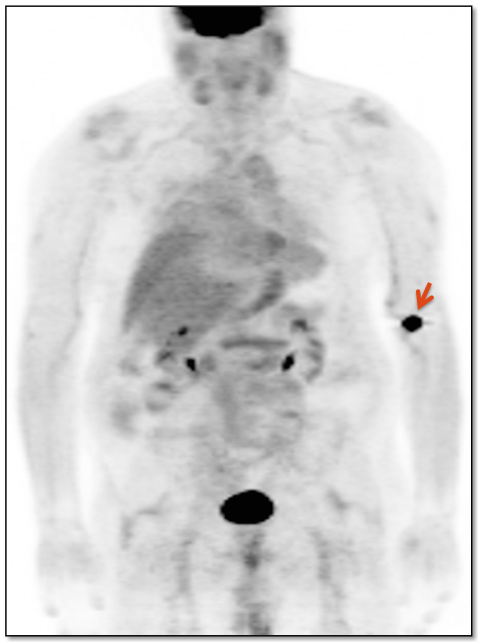

Extravasation of Injected FDG

FDG is injected intravenously. As many cancer patients have challenging venous access issues, partial extravasation of FDG during injection is not uncommon (an estimated 10% of patients have evidence of extravasation on their PET images).

Extravasation of FDG at the time of the intravenous injection can result in false positive interpretations due to:

- Focal intense uptake at the injection site.

- Linear uptake along the lymphatic channels within the arm (appearing as long vessels).

- Focal uptake in small ipsilateral axillary nodes.

If these nodes are enlarged, be cautious before dismissing them as “injection-related”. We have seen more than one case of a radiologist calling axillary nodes “injection-related”, when the patient was injected in the opposite arm.